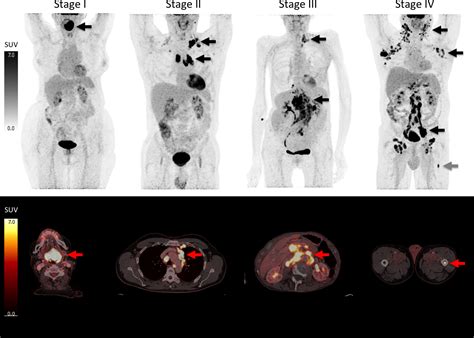

PET/CT Scan Helps identify the exact location and extent of the cancer throughout the body.